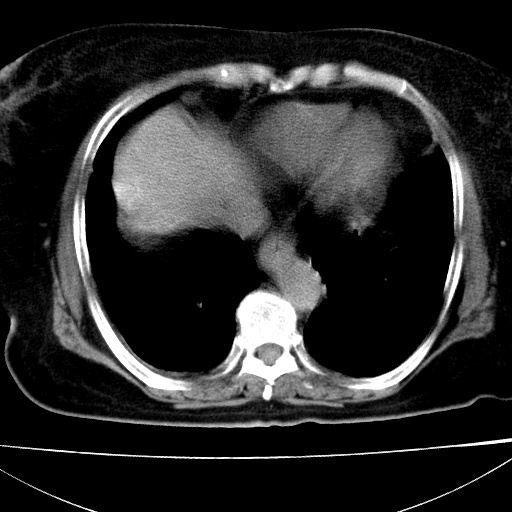

患者女74岁;右上腹胀痛1月,伴恶心,无发热;生活在疫水区。有术后病理及术后半年的追踪ct.

1)慢性血吸虫病(典型)。2)肝硬化。3)肝癌?4)胆囊炎。5)少量腹水。6)右侧少量胸腔积液。

支持.边缘见高密度线条样钙化影.

肝脏体积缩小,肝裂增宽,边缘不平呈波浪状,肝右叶见分隔状条索形钙化,亦见多结节低密度灶,边界不清,肝周可见少许液性暗区,胆囊增大内密度均匀,脾脏下缘低于脏脏的下缘,胸腔亦见液性暗区,余未见明显异常.

诊断:1肝硬化并慢性吸血虫病,脾肿大

2肝内占位,考虑肝癌可能性大,建议做增强

3胆囊炎, 4少量腹水及胸水

胆囊增大饱满,壁增厚。胆囊颈部见软组织密度影。临近肝右叶前段见片状低密度区,病灶下部见条状钙化,少量胸腹腔积液。意见:胆囊颈癌累及肝脏。

病人以胆囊癌手术的,病理结果为中分化腺癌。

现在看看肝右叶内圆形低密度影你们考虑什么呢?

肝内圆形低密度影考虑扩张的胆管

请看3mm重建像如下: